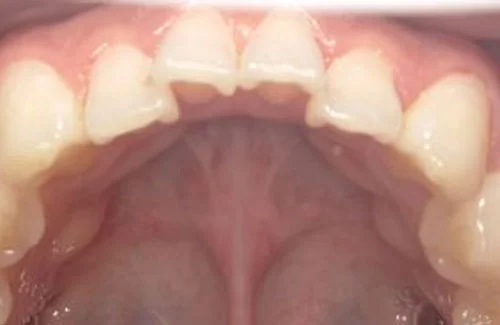

<症例7>歯がガタガタで噛み合わせが悪くお悩み

抜歯無し・マウスピースのみで矯正した症例です。

もともと歯列弓が非常に狭く、V字に近い形をしていたので噛み合わせも非常に不安定でした。

また、下顎前歯部がかなり上の方に生えていたため、下の前歯が上の前歯を突き上げてしまい出っ歯の状態になっていました。

現在では見た目はもちろん、臼歯の噛み合わせも改善しております。

患者様と症状

主訴:歯のガタガタ、噛み合わせが悪い

性別・年齢:20代女性

問題点:叢生(重度)、V字歯列弓、ディープバイト

診断:前歯部の叢生を伴うアングルⅠ級、骨格性Ⅰ級の不正咬合

主なリスク:臼歯の移動に伴い一時的に咬合しにくくなる、歯肉退縮

症状:叢生(そうせい) 過蓋咬合(かがいこうごう)

治療内容

治療期間:1年10ヶ月

治療費用:990,000円(税込)

プラン:Full2プラン

抜歯:無し

再診治療費:無し

追加治療費:無し

保定装置費:無し

治療前後の写真